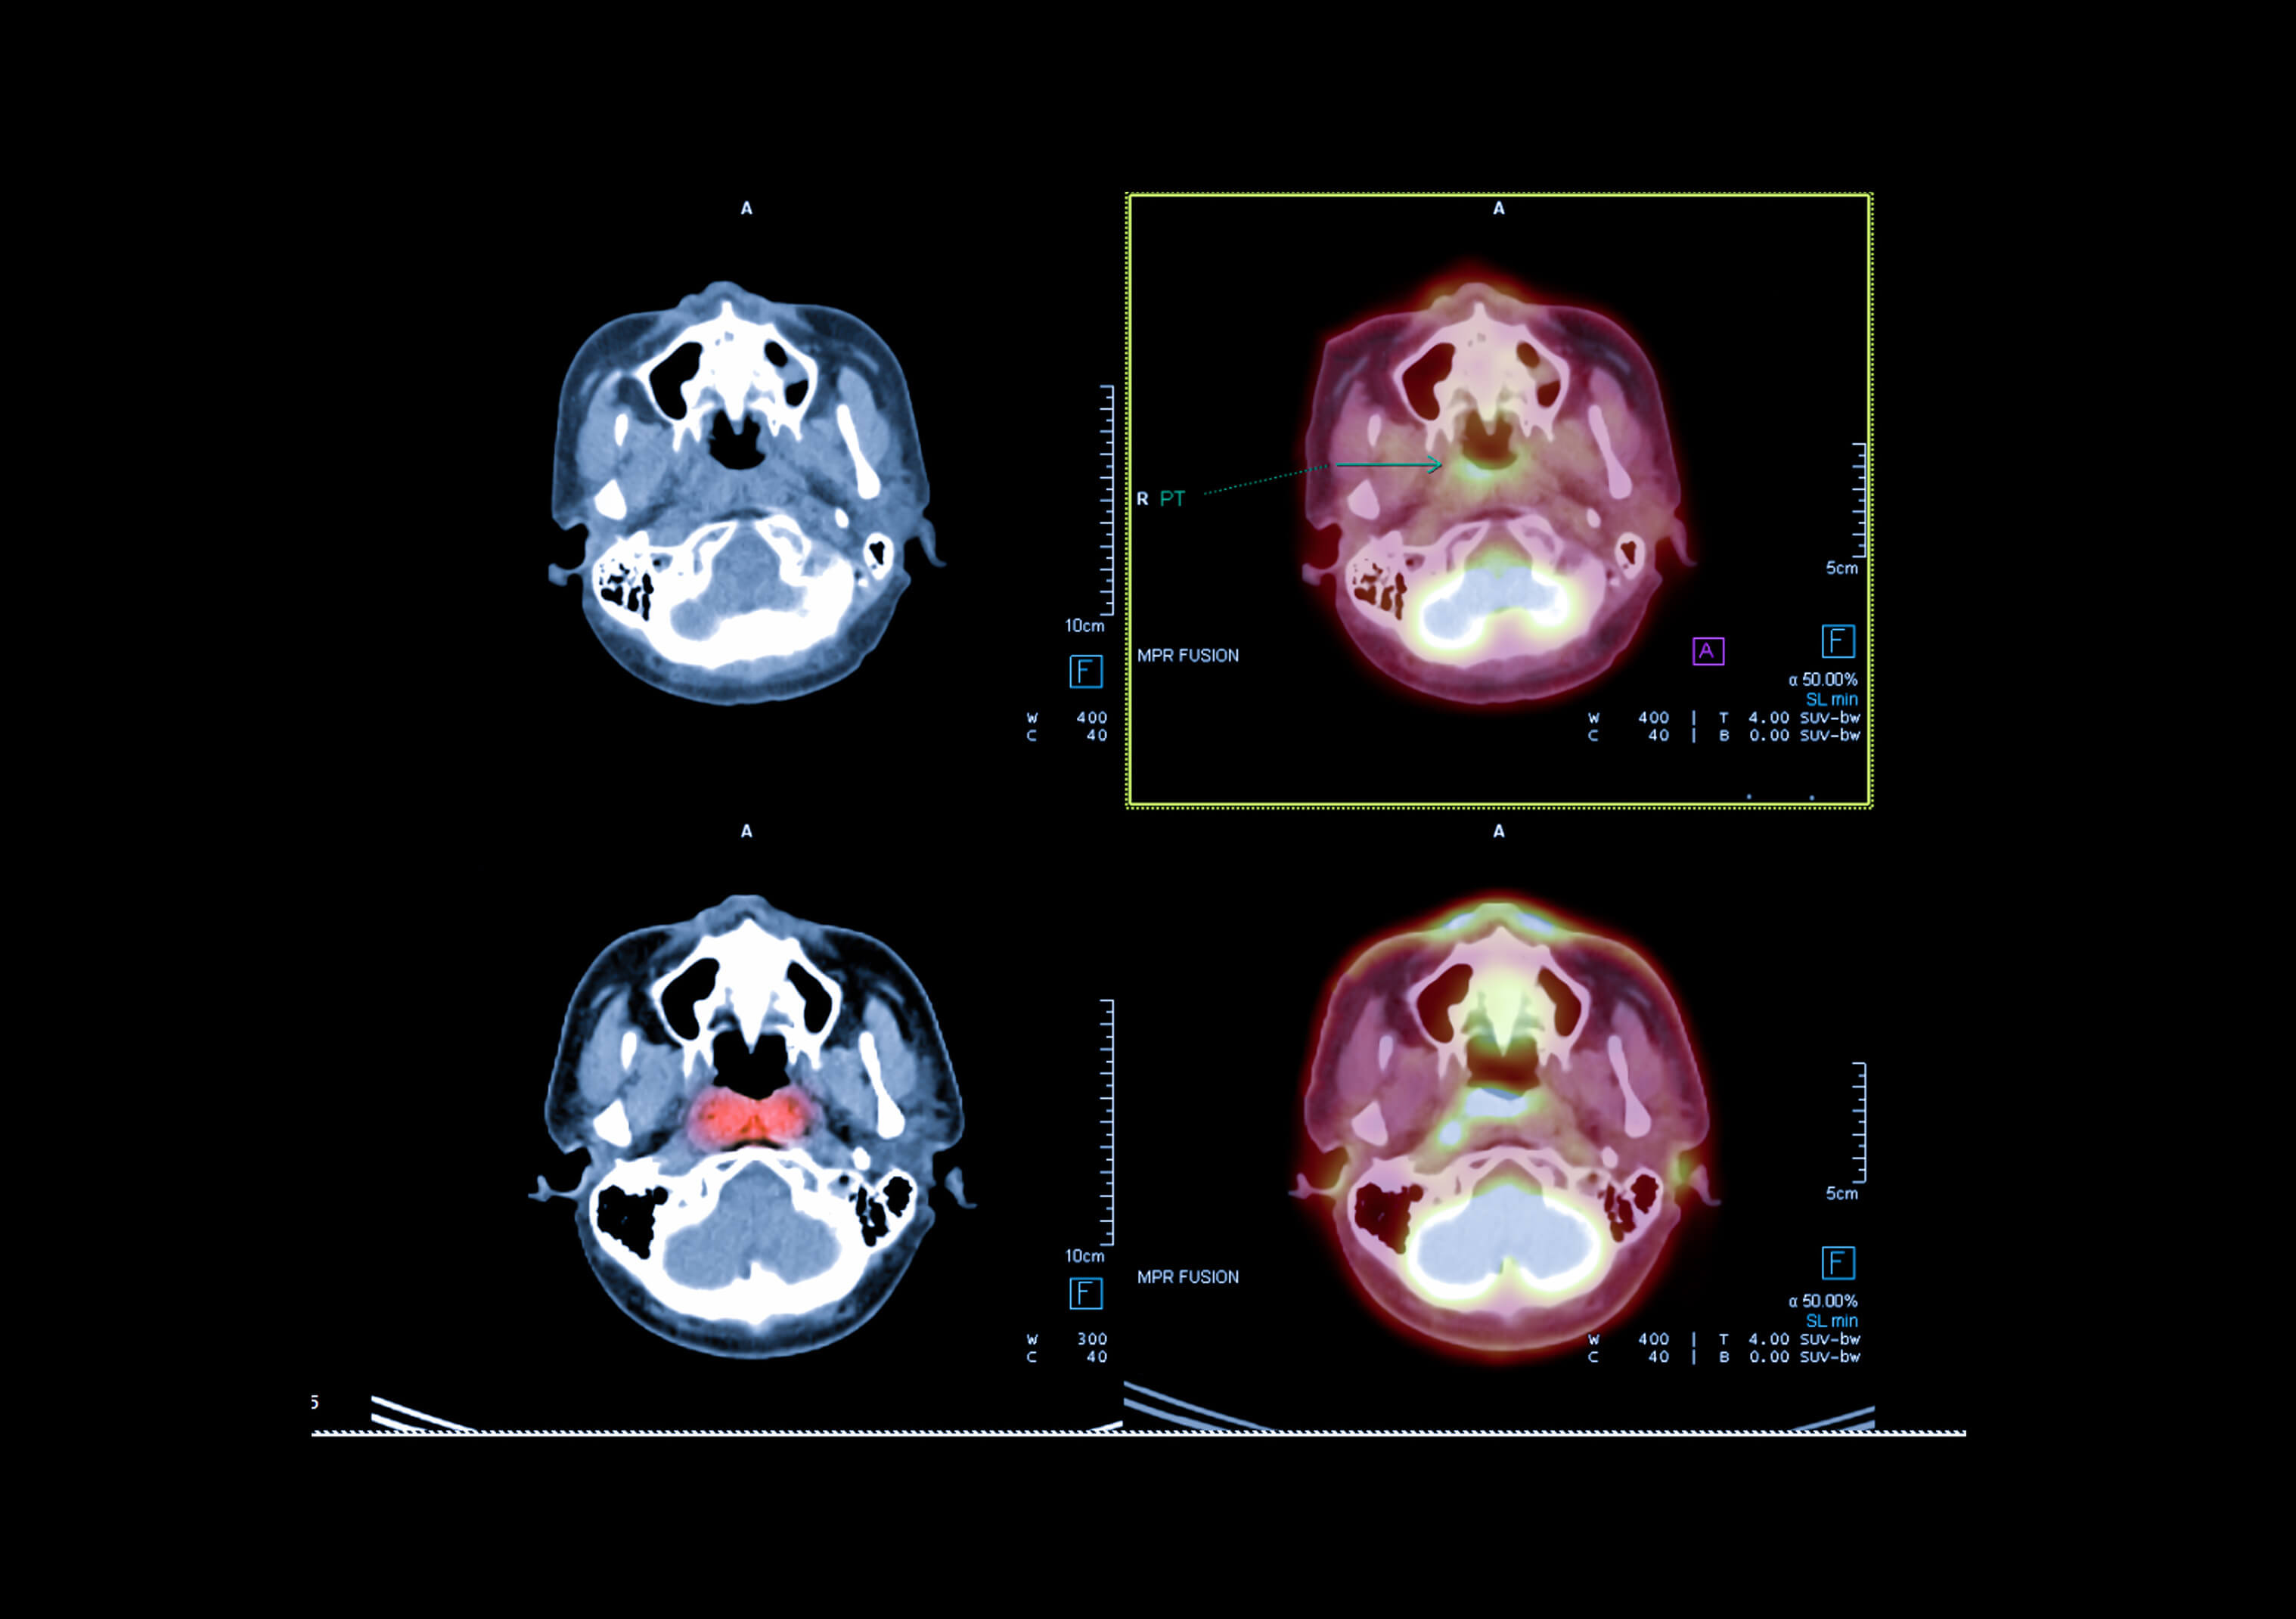

Le PET-CT associe deux technologies complémentaires : la tomographie par émission de positons (PET), qui apporte des informations sur l’activité métabolique et / ou le fonctionnement des cellules, et la tomodensitométrie (ou scanner, encore appelé CT), qui fournit des données anatomiques précises. La fusion de ces deux modalités d’imagerie va permettre de détecter avec une plus grande efficacité et de localiser avec précision des anomalies parfois invisibles à l’imagerie conventionnelle, et ceci lors d’un seul et même examen.

L’acquisition des images PET fait suite à l’injection d’une faible dose de traceur radioactif (sans effet secondaire pour l’organisme), le plus souvent du fluorodésoxyglucose (FDG), un analogue du glucose. Le FDG est capté en plus grande quantité par les cellules ayant une consommation accrue de glucose, notamment les cellules inflammatoires et la plupart des cellules cancéreuses. La désintégration radioactive du FDG va aboutir à l’émission de positons et de rayonnements gamma qui vont être récupérés via un anneau de détecteurs spécifiques afin de réaliser une image en 3 dimensions (3D) de la répartition du radiotraceur dans le corps du patient.

En parallèle, le scanner utilise des rayons X pour fournir des images anatomiques précises des tissus et organes. Ces données anatomiques en 3D sont superposées à l’image fonctionnelle tridimensionnelle obtenue par le PET, permettant ainsi une localisation fine des organes et éventuelles anomalies. En fonction des données cliniques et des antécédents spécifiques à chaque patient, le CT pourra être réalisé avec ou sans injection de produit de contraste iodé, cette injection ayant pour but de mieux visualiser certaines structures internes.

Cette approche intégrée permet d’améliorer les performances de détection de lésions tumorales primitives et de rechercher d’éventuelles métastases afin d’optimiser la prise en charge thérapeutique aux différents stades de la maladie : diagnostic, surveillance après traitement (notamment après chimiothérapie), recherche d’une éventuelle récidive. Le PET-CT va parfois permettre d’orienter les biopsies sur les lésions les plus agressives pour mieux caractériser l’atteinte tumorale. Dans d’autres cas, il peut permettre d’éviter des biopsies inutiles. Les informations issues du PET sont complémentaires à celles obtenues grâce au scanner : dans certains cas, l’efficacité du traitement pourra être mise en évidence par une diminution de l’activité métabolique dans la tumeur avant toute modification de sa taille.

En oncologie notamment, cela permet de mieux distinguer les tissus tumoraux actifs des structures anatomiques normales.

Les tumeurs les plus fréquemment évaluées par PET-CT sont les cancers du poumon, du sein, du cerveau, du côlon, de l’œsophage, du pancréas, les lymphomes, ou encore les tumeurs ORL.